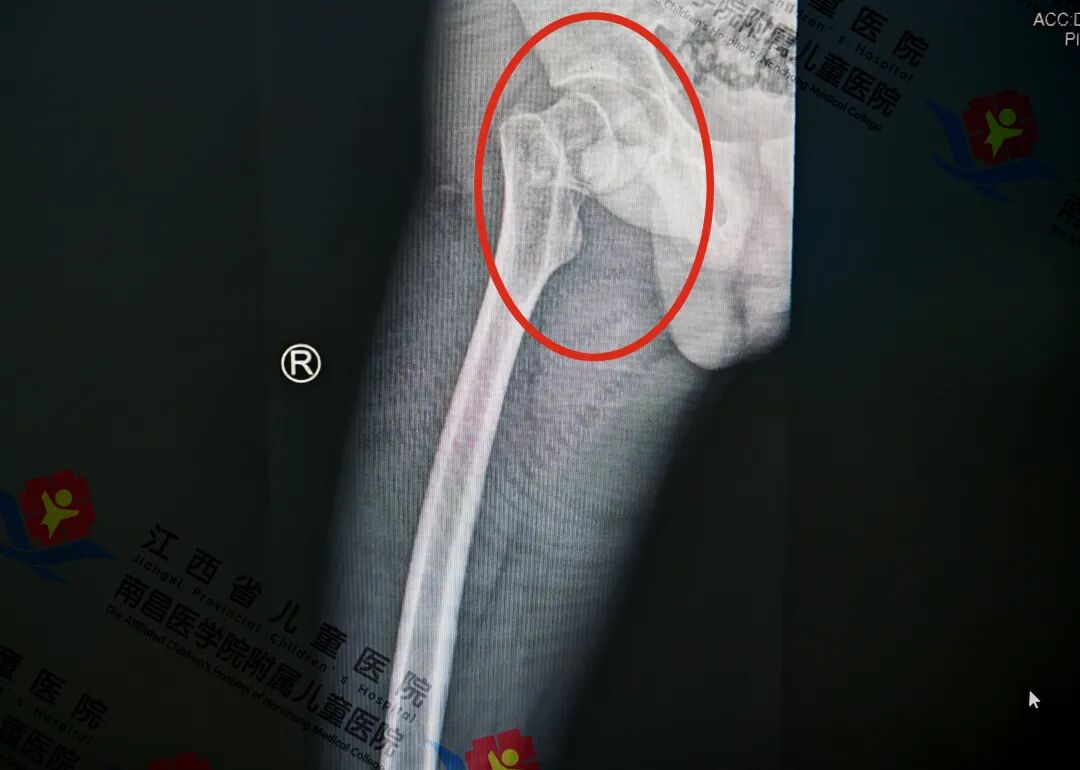

14岁男童摔出股骨颈骨折?精准定位+闭合复位技术“来救场”,微创治疗康复超省心!

近日,14岁男童小鸥玩耍时脚下突然一滑,整个人失去平衡重重地摔倒在地,右侧髋部直接着地。巨大的冲击力让他瞬间疼得龇牙咧嘴。起初家人以为只是普通摔伤,然而随着时间的推移,小鸥右侧髋部疼痛症状没有减轻,反而愈发剧烈,出现较为明显的肿胀。父母立即带其前来江西省儿童医院骨科门诊。副主任医师熊志刚发现小鸥右侧髋部有明显压痛且活动受限,为其右侧髋部进行详细检查检查结果显示为右侧股骨颈骨折。

术前

熊志刚介绍,股骨颈骨折在中老年群体中较为多发,而儿童股骨颈骨折则较少见。该骨折特指股骨颈部位的骨连续性发生中断,典型临床表现为大腿疼痛、局部肿胀、肢体畸形及活动功能受限。其致病因素多为车祸伤、坠落伤等高能量损伤。尤为值得注意的是,此类骨折后极易出现骨不愈合、骨坏死等问题,进而造成较高的致残率,需高度重视并采取科学规范的诊疗措施。副主任医师熊志刚、邹俊团队综合评估小鸥的骨折类型、生长规律、功能恢复程度等情况,并就治疗方案展开讨论,确定采用闭合复位的手术治疗方案。该方案为微创治疗,精准定位进针方向、创伤小、出血少、恢复快。